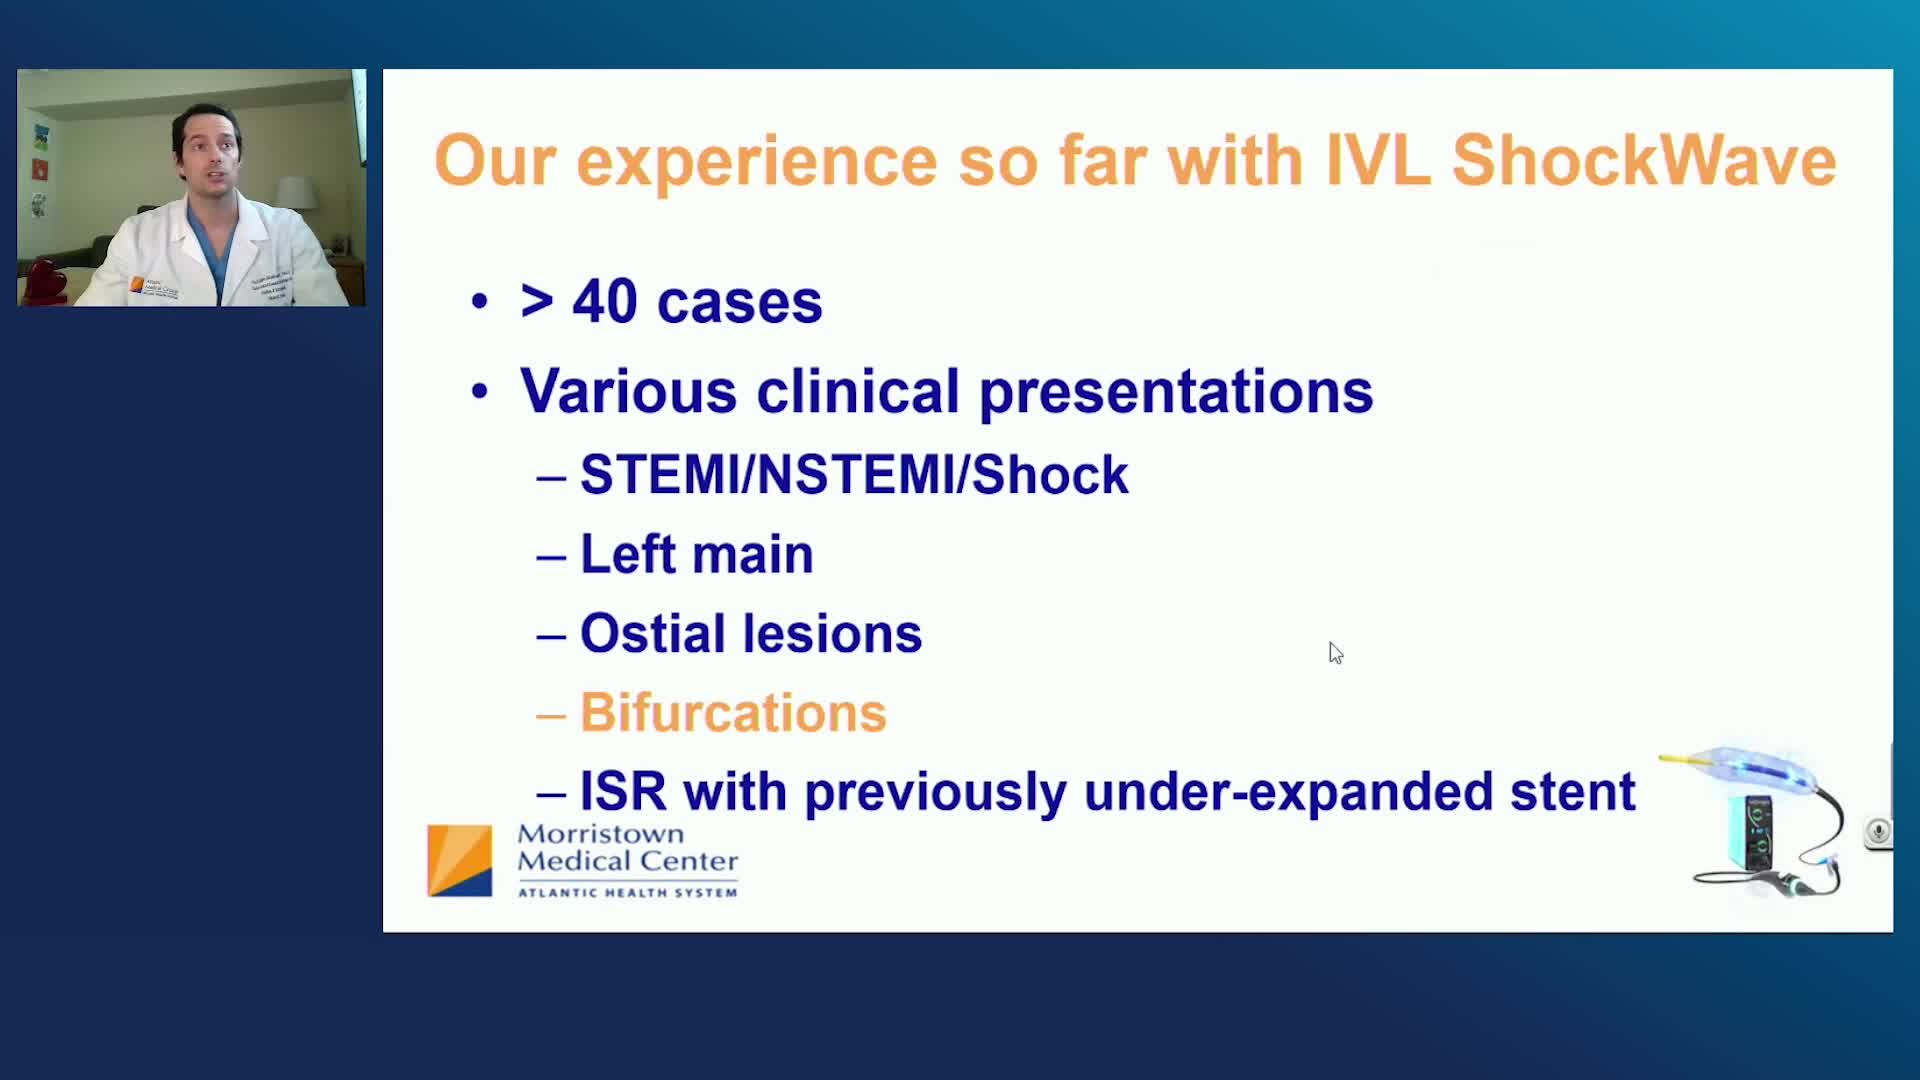

Shockwave IVL Coronary Real-World Cases, Outcomes & Algorithms: An InCathLab Webinar

Shockwave IVL